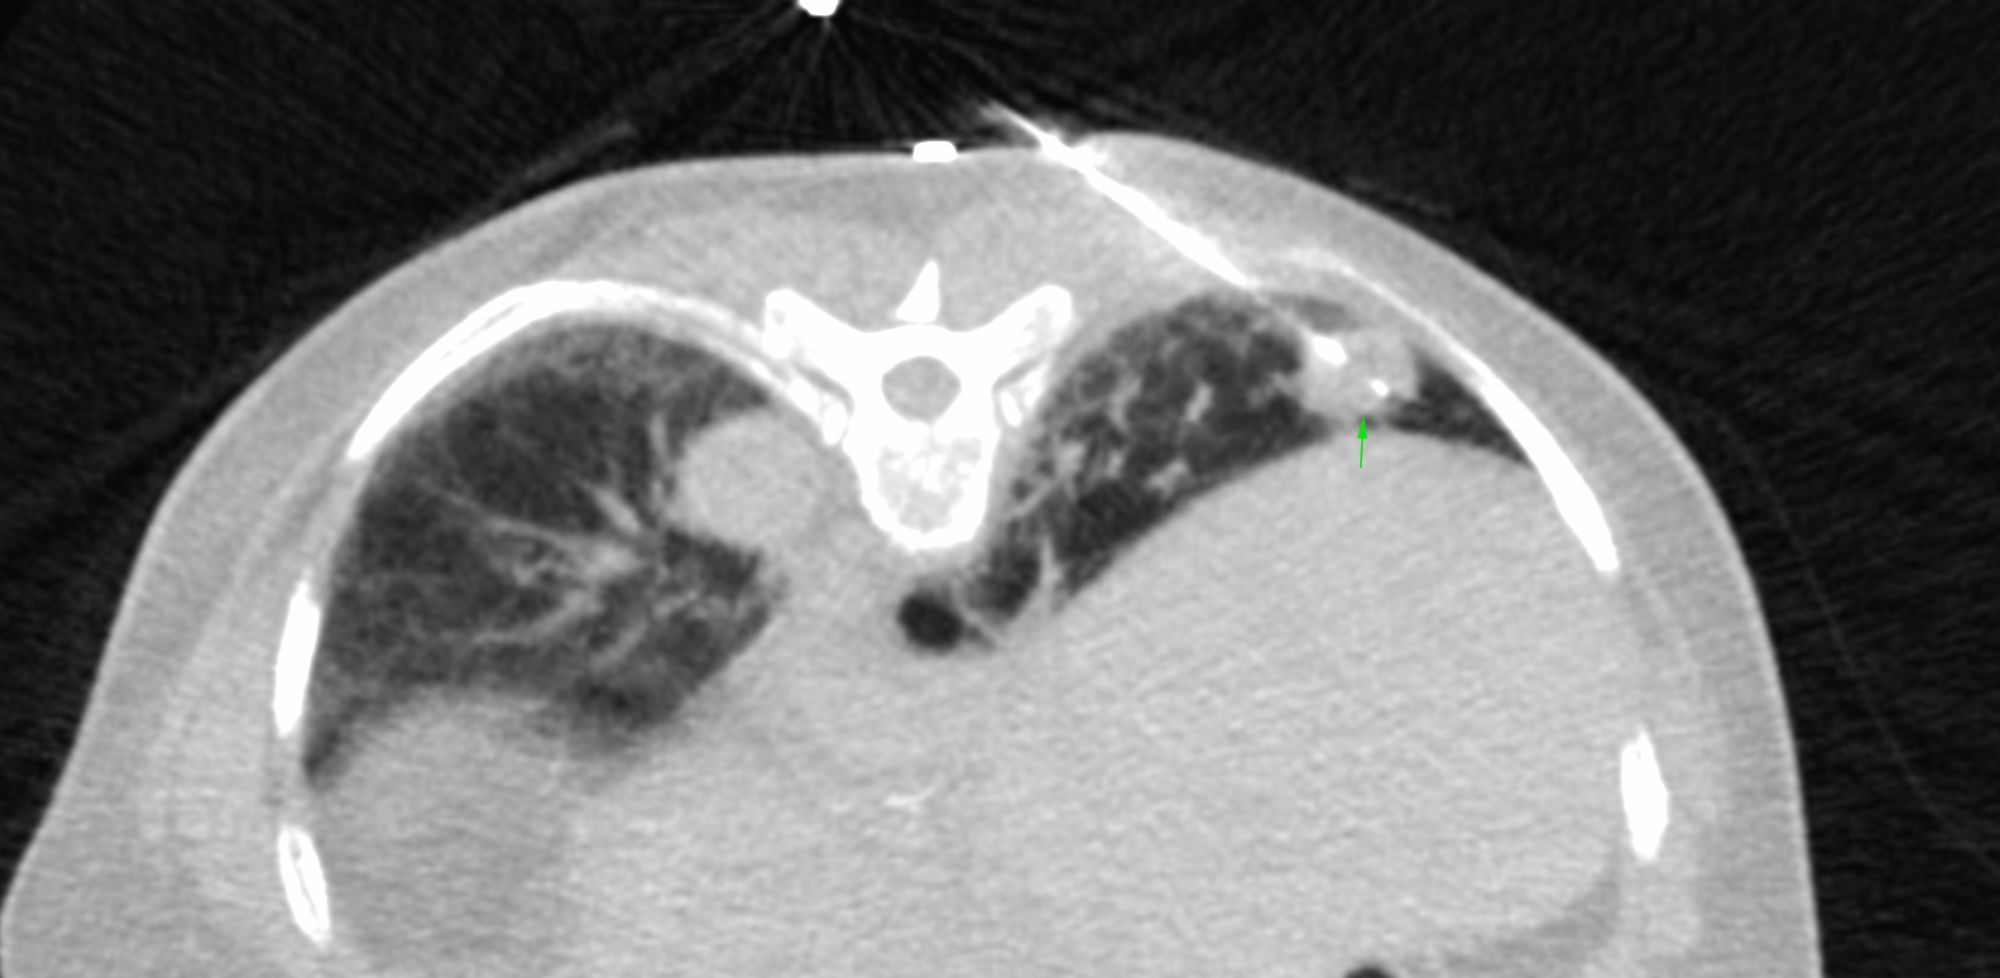

Case 17: 15 mm Lung Nodule Biopsy - Multiple Lung Nodules

Case 15: UIP IPF with a Superimposed Lung Nodule